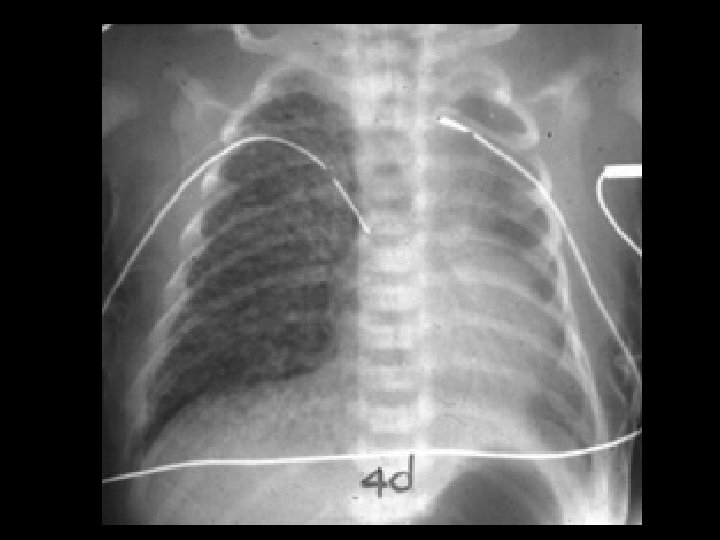

Hyaline Membrane Disease (HMD) • Findings: – symmetric, homogeneous “ground glass” appearance – air-bronchograms – decreased lung volumes • Pre-term infants with sufactant deficiency • generalized capillary leak • ddx: – neonatal pneumonia – transient tachypnea of the newborn – meconium aspiration

Neonatal Pneumonia • Findings: – diffuse bilateral granular opacities – normal lung volumes • Assoc/w PROM, mom (+) • Can lead to septicemia, shock, and death quickly • Classically Group B Strep • ddx: – TTN – HMD – meconium aspiration

Meconium Aspiration • Findings: – coarse and patchy densities with areas of overinflation and peripheral air-trapping • Normal fetuses with prepartum distress and hypoxemia release meconium and aspirate it • ddx: – HMD – neonatal pneumonia – TTN